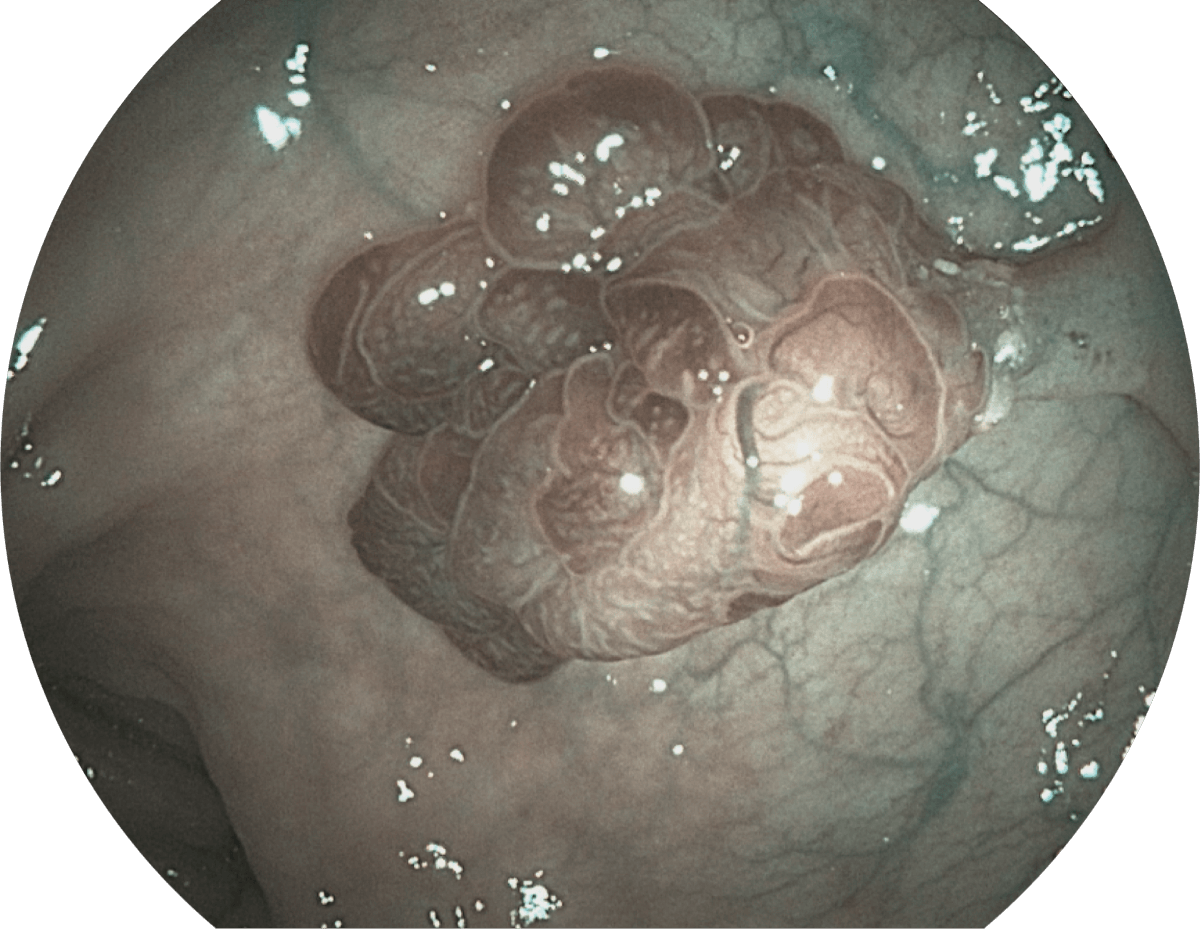

具有聚谱成像技术(SFI)及光电复合染色成像技术(VIST),可完美呈现粘膜细节及病变特征。

( Versatile Intelligent Staining Technology, VIST )

WL

SFI

VIST